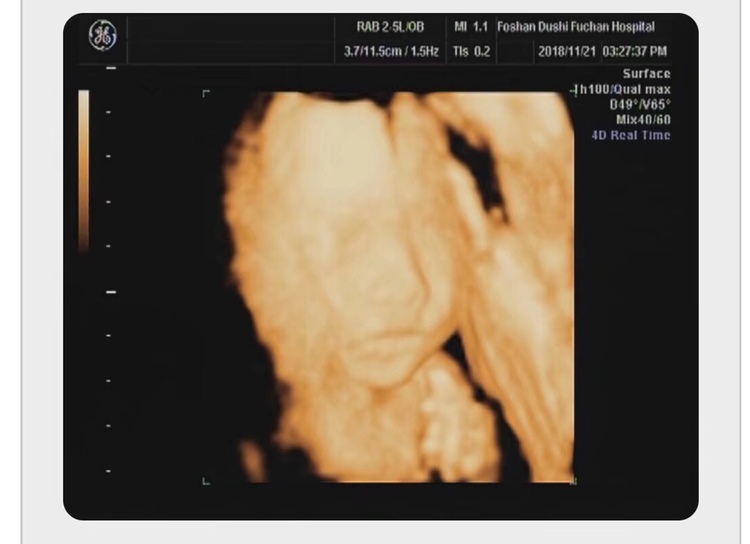

孕27周+0天

一模一样哦

孕31周+0天

孕26周+0天

很像